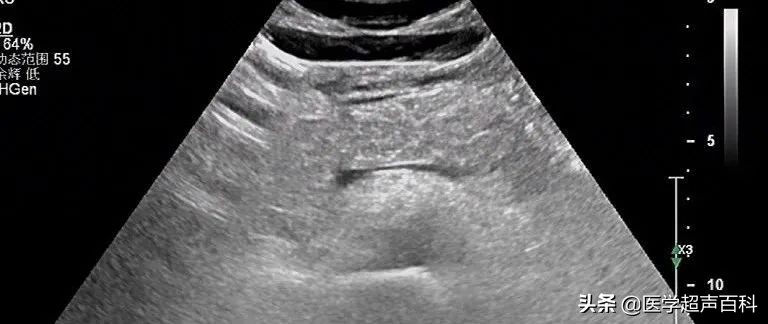

水肿型胰腺炎:胰腺稍大, 边缘规整,胰头、体部回声减低,分布前均质

水肿型胰腺炎:胰腺弥漫性增大,边缘形态规整,内部回声减低,胰腺后方血管受压迫显示不清

急性胰腺炎声像图表现

(1)胰腺弥漫性或局限性增大,可失去正常形态,轮廓不清。

(2)内回声减低,呈弥漫分布的弱点状,中间有强弱不均、形态不整、边界不清的片状回声。严重水肿时呈透声暗区,似囊肿声像图。

(3)多伴胰腺区胃肠气体增多,以胰头区更甚,使探查更为困难。